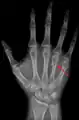

Fourth metacarpal of the left hand (shown in red). Palmar view.

The fourth metacarpal. (Left.)